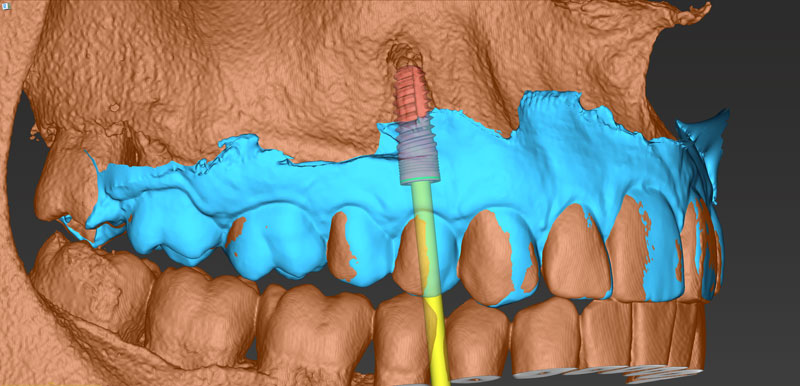

Ψηφιακό πλάνο θεραπείας

Κατευθυνόμενη τοποθέτηση εμφυτευμάτων

Είδη και ακρίβεια χειρουργικού οδηγού

Σχεδιασμός χειρουργικού οδηγού